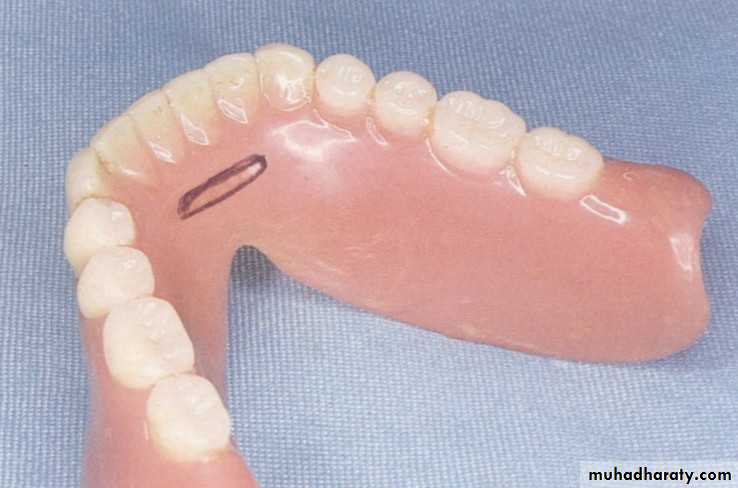

Treatment of choice: [Mandibular tongue prostheses*

Define as: dome-shape prosthesis fills the palatal vault, as much as normal tongue when mouth closed.Types:

For speech: should have ant. elevation to facilitate articulation of ant. linguo-alveolar sounds, /t/ & /d/. it also should have posterior one to articulate for linguo-palatal sounds, /g/ & /k/. Both improve vowel production.

For swallowing: should be sloped posteriorly to guide food to pharynx.

For both speech & swallowing: both types of TP can fabricate as interchangeable speech & swallowing prostheses attached via the retentive button on the base portion (this used for highly motivated patient).Source: Taylor. Th. 2000.

In mandibular TP, checking for adequate palatal contact of the tongue.

And ensuring freedom in lateral and protrusive movements.Some important notes